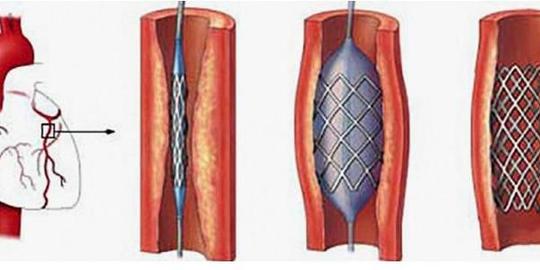

冠状动脉造影术

【医学科普】带你一起进入冠脉造影和心脏支架植入现场

冠状动脉造影

(冠状动脉造影检查)

心脏造影检查血管堵塞多少做支架

【专病专讲】冠心病之冠脉造影检查

得了冠心病,到底做心脏造影还是cta,了解这些

冠脉造影医保报销比例冠县社保局【心科普】为什么要做冠脉造影检查